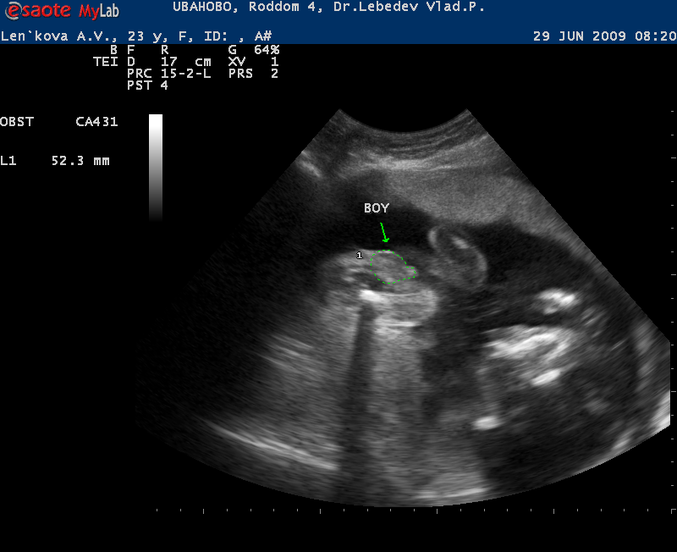

эМ

точно, ни с чем не спутать)) у нас мальчики и тоже как на яву было, всё как у папы, ни с чем не спутать))

это мальчишечка))) даже место расположение по костям бедренным не как у девочки на узи) а как бы вперед выдвинуто, и дочи на вссех узи пися прям вот посередине, и от нее ножки сразу)))) ну и форма.. я прям и на мониторе видела и на фотках на всех сроках с 16 недель четко видно овал такой пухлый очень близкий к кругляшку... ) ну всякое бывает наверное) но видимо теперь у вас будет 2 помощника)) здоровья вам с малышом